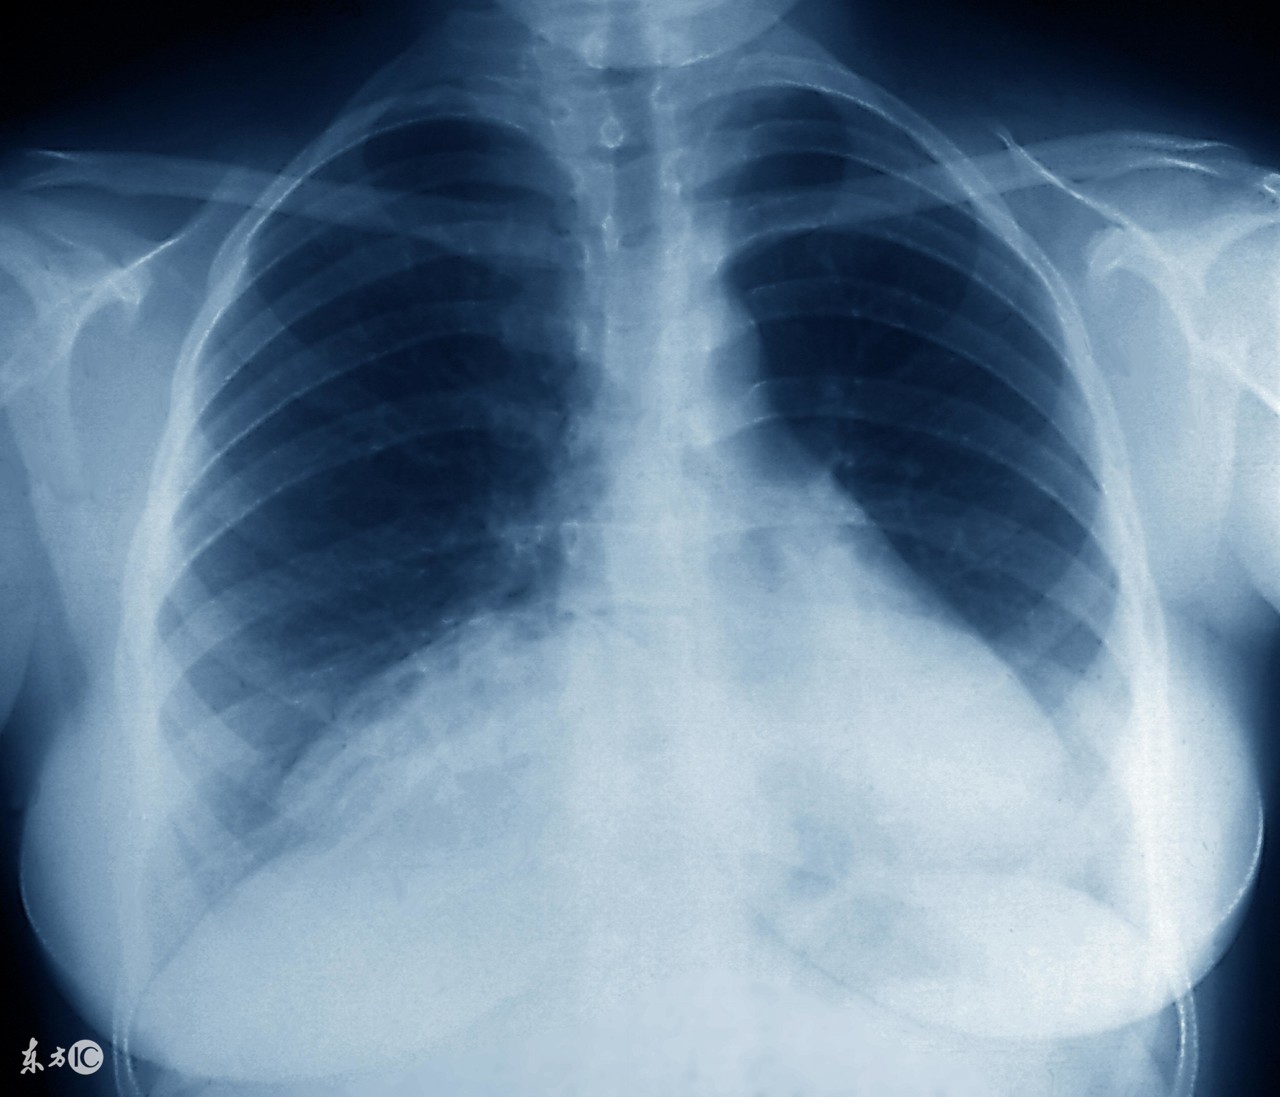

支原体肺炎和其它肺炎疾病一样,是需要及时对症治疗的,支原体肺炎患上之后就引起长期的低烧和畏寒等情况,及时对症治疗才是最关键的,由于治疗不当或是滥用药物都会引起支原体肺炎,面对复发的支原体肺炎,患者要消除病因,利用抗生素抑制病情。那么,支原体肺炎反复发作怎么治疗最佳?下面来了解吧。

必须强调的是,常用于治疗支原体肺炎的青霉素类和头孢菌素类抗生素,其抗菌原理为阻止细胞壁合成。支原体肺炎主要是由于肺炎支原体呼吸道感染而引起的肺部感染,是较为常见的肺部炎症,临床上对于较轻的患者一般可以自愈,较为严重的患者一般用抗菌药物进行治疗,较为常用的药物为大环内酯类药物。

对支原体肺炎病情严重有缺氧表现者,或气道梗阻现象严重者,应及时给氧。方法与一般肺炎相同。